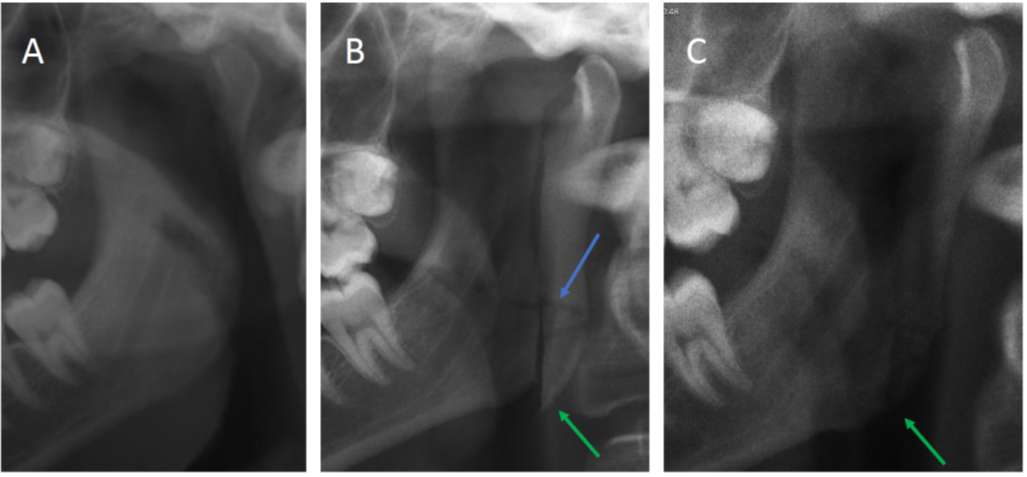

Upprinnelsen till den modifierade kondylotomin är inte helt klar, men sannolikt började metoden användas under 1940-50-tal i Storbritannien för att avhjälpa käkledsbesvär [1]. Initialt var indikationen upprepade luxationer av käkleden samt symptomgivande artros. Operationen gjordes ofta slutet med en s k Gigli-såg genom att processus condylaris sågades av på den symptomgivande sidan. På detta sätt droppar kondylen ner och ledutrymmet ökar. Den öppna modifierade kondylotomin, där man gör en vertikal osteotomi i ramus mandibulae, började användas i slutet på 1980-talet för att behandla diskdisplacering utan återgång (Figur 1) [2]. På så sätt minskas belastningen på käkledsdisken och knäppning/upphakning elimineras.